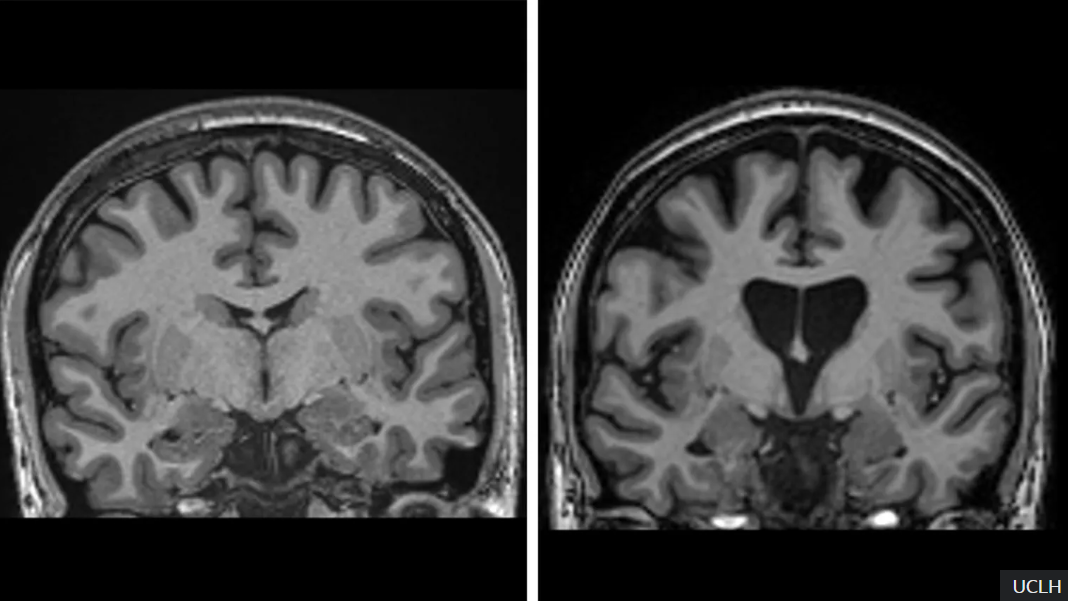

이번 임상시험은 uniQure와 유니버시티 칼리지 런던(UCL) 연구진이 협력하여 진행했습니다. 치료는 변형된 바이러스를 통해 뇌세포에 DNA를 전달하여, 독성 단백질 ‘헌팅틴(huntingtin)’의 생성을 차단하는 방식으로 이루어집니다. 수술은 12~20시간 동안 정밀하게 진행되며, 단 한 번의 주입으로 효과를 발휘합니다.

임상시험에 참여한 29명의 환자 중 고용량 치료군은 평균 75%의 진행 억제 효과를 보였습니다. 이는 운동 능력, 기억력, 인지 기능 등 다양한 지표에서 입증되었습니다.